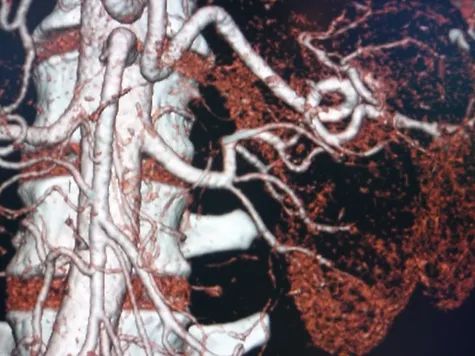

A hormone-secreting tumour that can occur in the adrenal glands. Phaeochromocytomas usually develop in the small glands on top of the kidneys (adrenal glands). They most commonly affect people between the ages of 20 and 50, but can occur at any age. Because of hormones secreted, symptoms include high blood pressure, sweating, rapid heartbeat and headache. Surgery to remove the tumour is usually required.